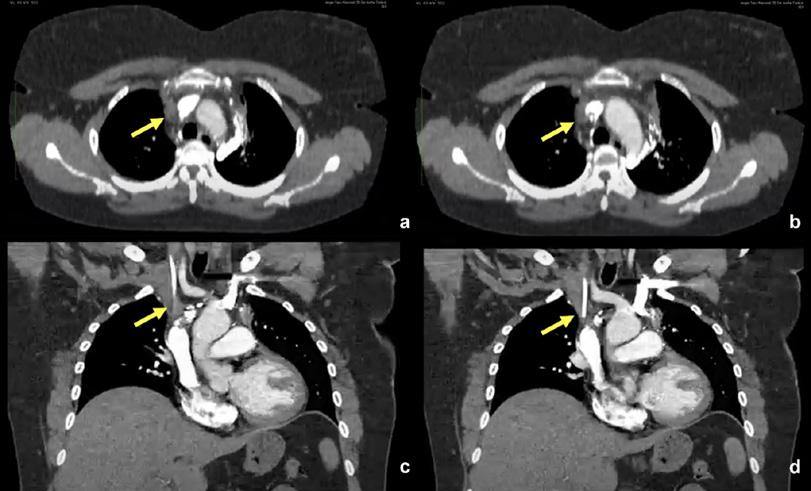

Llama la atención, en las adquisiciones de perfusión, la presencia de captación anómala del MAA-Tc99m proyectada posteriormente en la línea media superior de la caja torácica, en relación de vértebras torácicas.

Esta captación es esperable visualizarla en las imágenes ventilatorias de este estudio por deglución del trazador en esófago o depósito en vía aérea principal, pero no en la etapa perfusoria (Fig. 1 y 2).

Figura 2. SPECT de perfusión pulmonar. Múltiples imágenes del SPECT de perfusión pulmonar en los tres planos, muestran el aumento de la concentración del radiotrazador en cuerpos vertebrales dorsales (flechas rojas).

Figura 1. Imágenes planares de Ventilación (arriba) y perfusión (abajo) pulmonares. No se evidencian defectos perfusorios mismatch entre ambas fases. Se destaca el aumento de captación del MAA